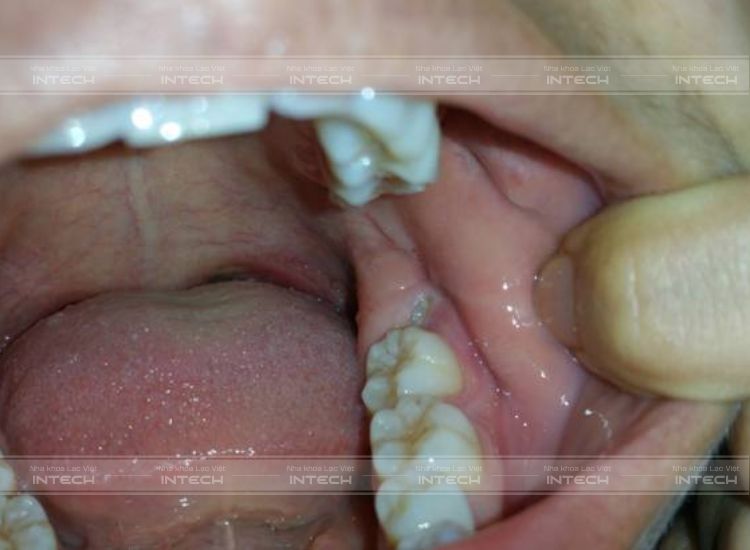

Răng khôn gây ra nhiều rắc rối ảnh hưởng đến sức khỏe răng miệng cũng như ảnh hưởng đến sức khỏe toàn thân. Do đó, bạn nên tránh những điều dưới đây:

Trong giai đoạn răng khôn đang mọc, bạn tuyệt đối không được có các tác động mạnh vào cung hàm như: đánh răng quá mạnh, dùng tăm xỉa vào vị trí mọc răng khôn,... vì có thể dẫn đến tình trạng chảy máu, tăng nguy cơ gây viêm.